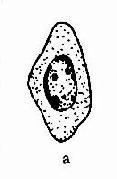

(五)未成熟的生殖细胞(见图11-2)

未成熟的男性生殖细胞即生精细胞,包括精原细胞、初级精母细胞、次级精母的细胞和以育不完全的精子细胞。这神经过敏细胞胞体较大,常有1-2个核,有时易与中性粒细胞相混淆,尤其是用未染色精液镜检时不易识别,需在时可用过氧化物酶染色鉴别,前者为阴性,后者为阳性,正常人未成熟精细胞<1%。当曲细精管受到药物或其它因素的影响或损害时,精液压中可见较多的病理型生精细胞。(见图11-3)。

图 图11-2 正常生精细胞

图11-3 异常生精细胞